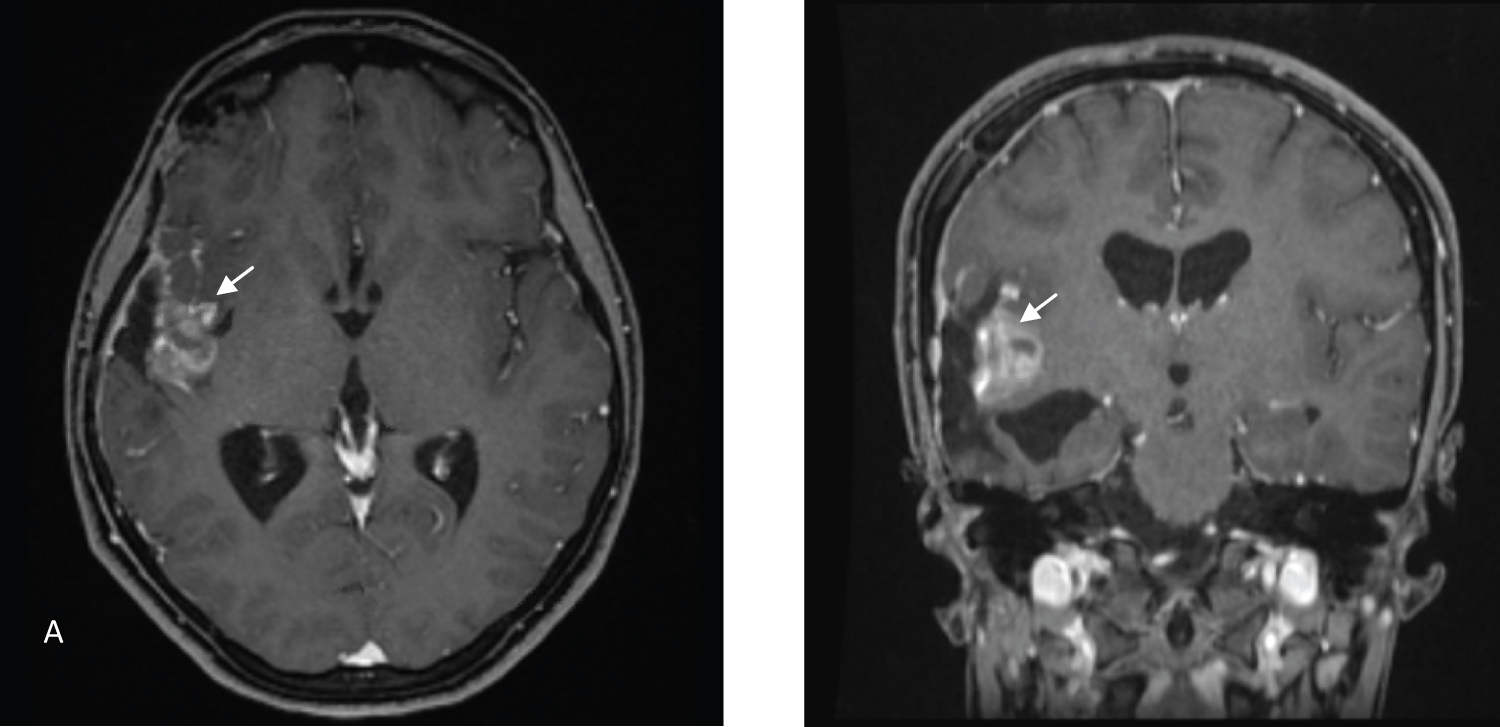

MRI of the brain (Figure 1) showed a mass measuring 5.1*5.6*5.4 cm in the anteroposterior, transverse, and craniocaudal dimensions. The mass was heterogeneous, showing moderate enhancement and a few foci of calcification and hemorrhage. The lesion was centered in the right Sylvian cistern, invading the insula and right frontal and temporal lobes. The mass abutted the dura, without a dural tail. Multiple enlarged blood vessels were seen coursing through the mass. There were large arterial feeders from the dilated right MCA and draining veins leading to a dilated right superficial middle cerebral vein. MR perfusion demonstrated markedly raised perfusion seen within the mass.

Figure 1: Axial, coronal, and sagittal views (A,B,C) of contrast-enhanced T1 MRI. Axial view (D) of a T2 MRI sequence showing a right frontotemporal tumor (Arrows) with a significant mass effect and foci of hemorrhage and calcification. View Figure 1